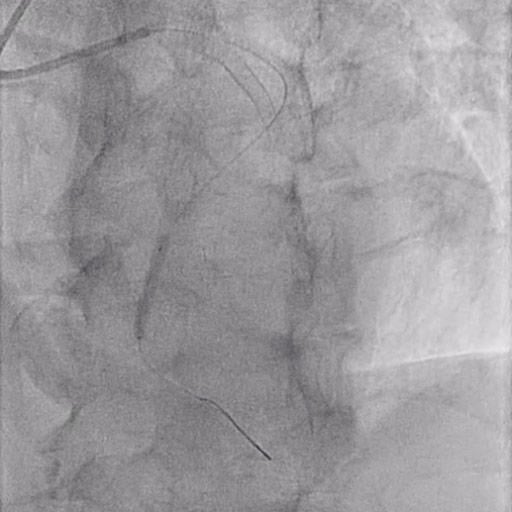

Figure 2: Lesion preparation

In case of a sub-optimal result, further dilatations can be performed at higher pressures (16-18 ATM), or other devices such as scoring or cutting balloons, lithotripsy, and atherectomy may be used.